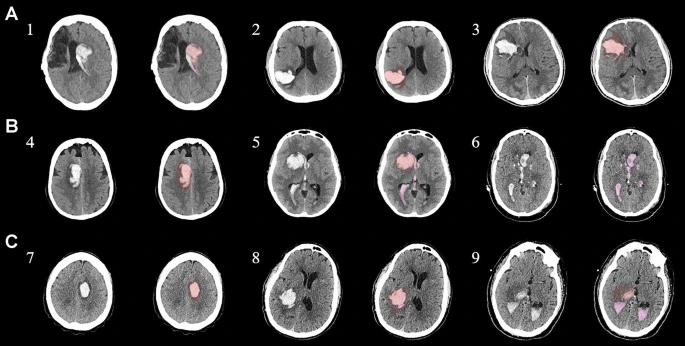

為了描述目的,患者按入組順序被賦予編號,并被連續(xù)分配到三組中的一組,每組三名。根據(jù)模型2分割,ICH體積范圍為0.1至54.9mL(平均ICH體積為23.5mL)。5名ICH患者受累于局限性腦葉,其余患者受累于基底神經(jīng)節(jié)或外囊深處。3名患者的ICH位于丘腦(圖1),1名患者的血腫位于多個腦結(jié)構(gòu)(即尾狀核、殼核和蒼白球)。平均而言,MSCs是在ICH后3天注射的。

結(jié)合臨床特征的探索性成像容積模型分析

ABC/2模型1和模型2分割方法均通過線性回歸顯示出ICH和IVH體積的良好相關(guān)性(圖3a、b)。與模型2分割體積方法(例如每CT15-20分鐘)相比,模型1ABC/2衍生的半定量方法和改進的Graeb IVH方法所需的時間更短(例如2-5分鐘)。有趣的是,將NIHSS評分與IVH體積M2方法進行比較顯示出線性相關(guān)性(R2=0.7217),并且當(dāng)IVH小于20mL或大于20mL時,NIHSS評分似乎存在聚集性(圖3c)。PHE 分析顯示MSC注射劑量與PHE體積之間存在輕微的負相關(guān)關(guān)系。